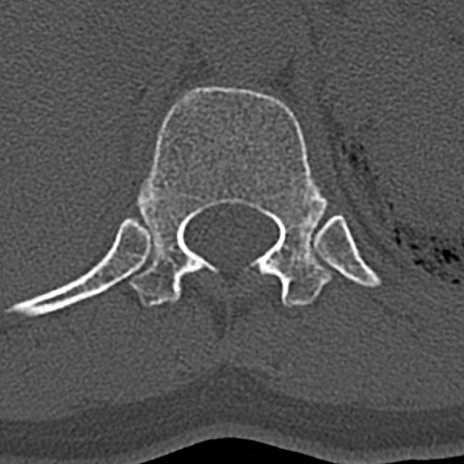

腰椎CT

横断像と矢状断像